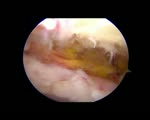

Artroscopia Hombro Izquierdo Rotura completa manguito rotadores Supraespinoso e Infraespinoso

artroscopia

hombro

medicina

supraespinoso

infraespinoso